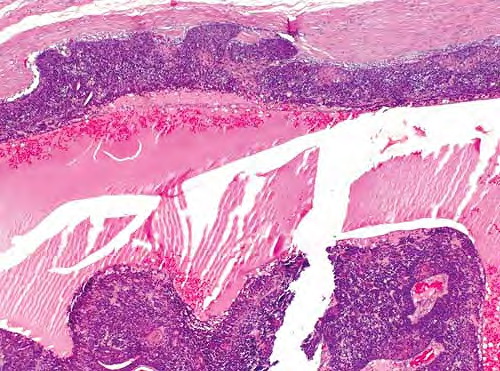

Digital papillary adenocarcinoma = غدوم حطاطي على الاصبع